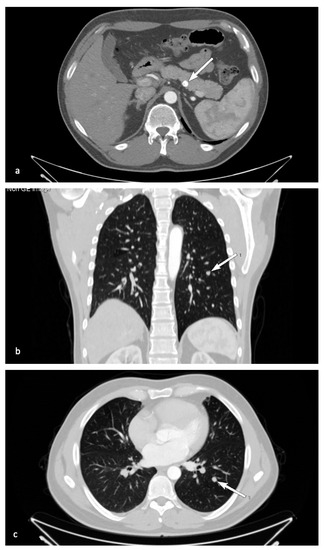

A son of the index patient’s brother, born in 1980, was diagnosed with MEN1 syndrome via cascade genetic screening. Since 2014, he had been suffering from nephrolithiasis and underwent percutaneous nephrolithotomy. Hypercalcemia in the course of primary hyperparathyroidism was confirmed and the patient underwent parathyroidectomy with resection of the upper right, lower right, and lower left parathyroid glands in April 2015, which subsequently resulted in iatrogenic hypoparathyroidism. Histopathological analysis confirmed the presence of parathyroid nodular hyperplasia. In 2014, bilateral adrenal tumors were detected in abdominal CT (24 mm in the left adrenal gland and 5 mm in the right, both characterized by radiological features of an adenoma), with no excessive hormonal function. Additionally, CT confirmed the presence of a pancreatic cyst, which was left in place for radiological follow-up. In 2015, MRI revealed a pituitary microadenoma, clinically and biochemically silent. During a follow-up visit in 2016, abdominal CT revealed a round 8-mm tumor with calcifications in the corpus of the pancreas (Figure 4a).

Figure 4.

Radiological presentation of patient III.4 in the pedigree. Transverse CT image of pancreas with calcifications (a) and lung metastasis in axial (b) and transverse (c) CT (arrows).

In November 2017, (68Ga) Ga-DOTATATE PET/CT was performed. It revealed multiple focal accumulations of the tracer in the pancreas, with the most prominent one observed within the pancreatic corpus (SUVmax 22.8), located in the topography of a previously described calcified tumor, and a probable metastasis in the left lung (SUVmax 6.54). In January 2018, due to dissemination of the neuroendocrine tumor, treatment with Lanreotide autogel at 120 mg s.c./4 weeks was initiated with good patient tolerance. In December 2018, an endoscopic ultrasound was performed. Histopathological examination of the samples revealed the presence of a probable neuroendocrine tumor (synaptophysin+, chromogranin+). In January 2020, follow-up CT revealed a partial regression of the pancreatic lesions, while the pancreatic neuroendocrine tumors and metastatic lung lesion were stable with no further progression (Figure 4b,c). Careful follow-up has been scheduled. Non-endocrine manifestations were seen as multiple cutaneous collagenomas.